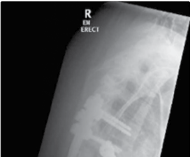

Figure 4.9 The knees-to-chest position for lumbar discectomy.